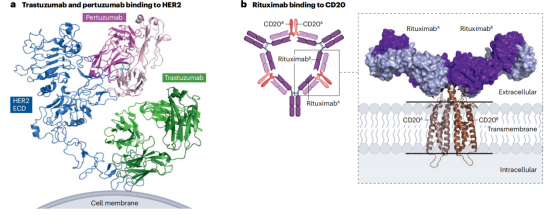

免疫检查点通过阻断抗体抑制负调节T细胞的途径,从而使细胞毒性T细胞重新活化,杀死癌细胞。已获得FDA或EMA批准的治疗性抗体靶向的三种蛋白或途径是CTLA4,PD1-PDL1和LAG3。PD1阻断抗体是目前使用最广泛的免疫检查点抑制剂。7种已获批的PD1阻断抗体和目前正在临床试验的两种使用IgG4格式,与IgG1同型相比,它不能有效激活补体级联,Fc受体结合较弱。因此,IgG4格式可能保护表达PD1的效应T细胞不被ADCC或CDC无意中杀死。所有IgG4抗体都携带S228P突变以防止Fab臂交换。通过结果生物学分析发现,PD1的2种阻断抗体pembrolizumab和nivolumab结合PD1的不同表位,并且与配体PDL1结合位点重叠,从而阻止PD1-PDL1相互作用。PDL1靶向抗体与PDL1和PDL2复合物的晶体结构鉴定了PDL2中一个关键残基(Trp100),该残基阻碍抗PDL1抗体与PDL2的结合,并提供了PDL1和PDL2之间的选择性机制。

两种CTLA4靶向抗体Ipilimumab和Tremeli-mumab具有相似的结合表位,可以有效地与天然配体CD80和CD86竞争。